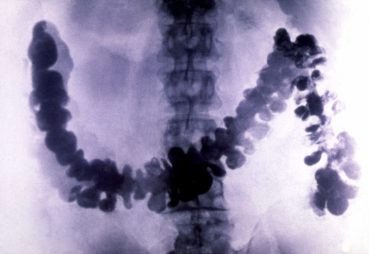

Рентгеновские снимки при ирригоскопии толстого кишечника